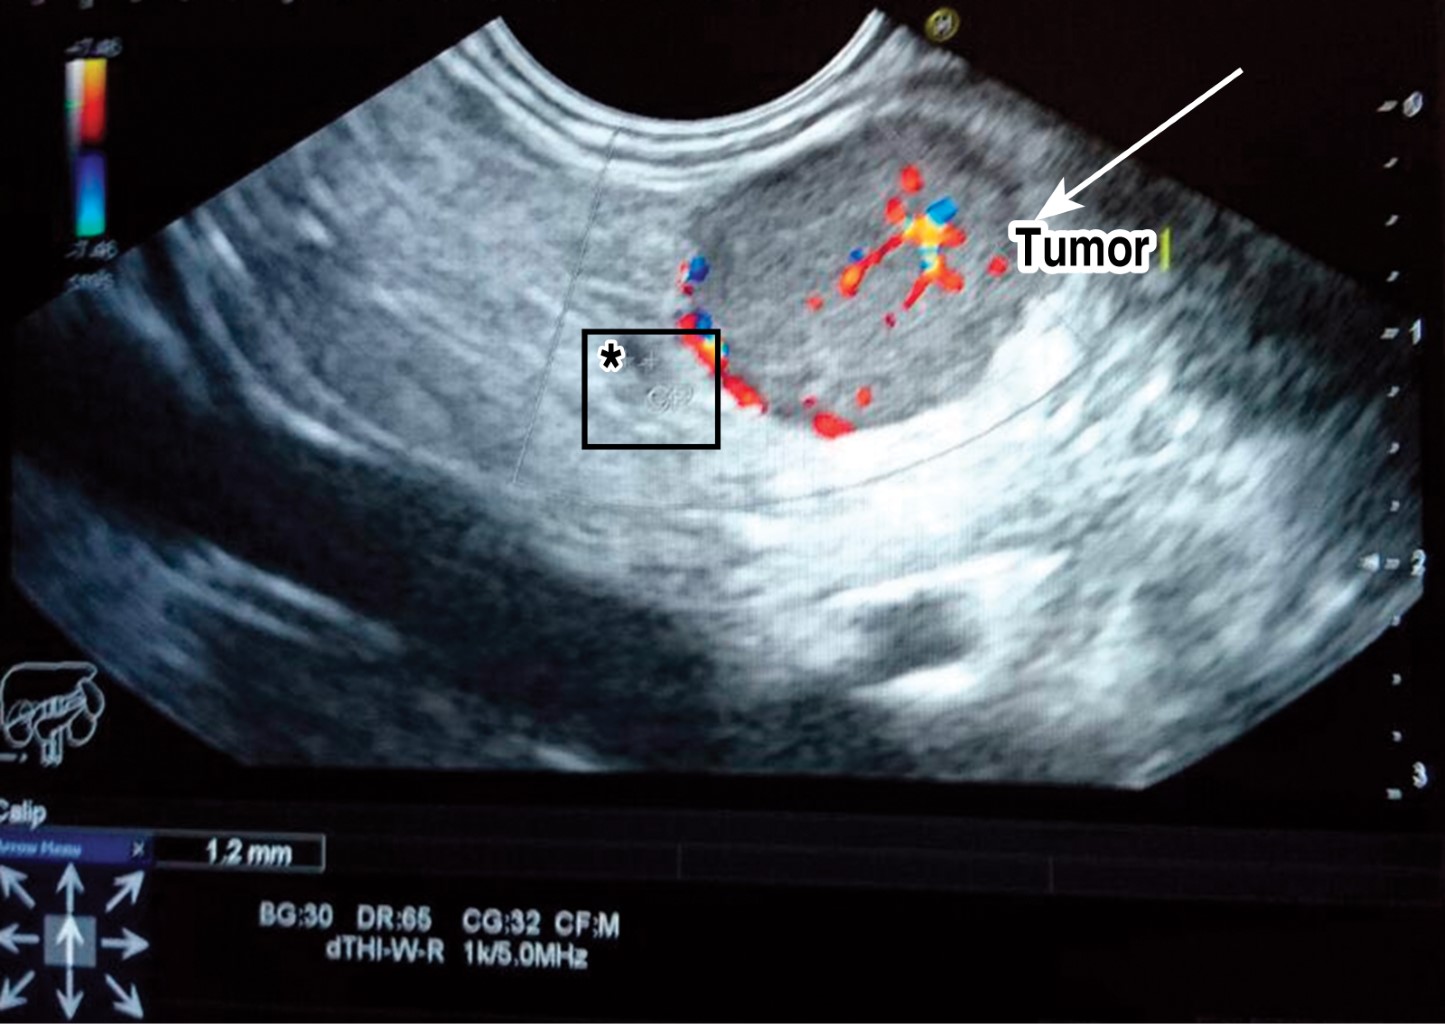

A 51-year-old woman with no significant family history. She started her condition three years before her hospital admission with intermittent episodes of diaphoresis and palpitations. On arrival, she reported an oppressive frontal headache and had a capillary glycemia of 28 mg/dl. Her symptoms improved after ingestion of glucose-rich food. She was admitted because of a seizure. Her thorax was found with no alterations, her abdomen with abundant adipose panniculus, soft, non-painful, peristalsis present and normal, and the rest of the examination also without pathological data. Her laboratory studies showed glycosylated hemoglobin of 4.5%, negative blood sulfonylureas, glucose 37 mg, insulin 64.1 IU/ml, C-peptide 8.36 ng/ml, TSH 1.8 IU/ml, T4L 1.11 ng/dl. A contrast-enhanced CT scan of the abdomen was reported normal. Magnetic resonance imaging (MRI) showed a nodular lesion between the head and body of the pancreas of 2.0 × 1.8 × 1.6 cm, which did not produce obstruction. Endoscopic ultrasound (Figure 1) corroborated the superficial location of the tumor, distant more than 2 mm from the splenic vessels and the pancreatic duct. Given its size and location, a laparoscopic enucleation was done. Pneumoperitoneum was produced, ports placed in the umbilicus (10 mm), another one for the hepatic retractor in the right anterior axillary line (10 mm), two left and one right port (5 mm). After dissection of the gastrocolic omentum, the stomach retracted upwards and the tumor was detected between the body and tail of the pancreas (Figure 2). Enucleation was done with a harmonic scalpel and the tumor was removed from the abdominal cavity using a bag through the assistant's port.

Figure 1